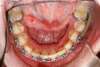

Fentes palatines bilatérales, cas traité au cabinet d'orthodontie du Dr Le petit à Bordeaux

Intra Orale Inférieure